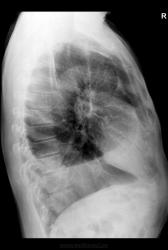

Мужчина, 56 лет. Состояние после нижней билобэктомии правого легкого по поводу центрального рака

1. В плевральной полости, безусловно, жидкость.

2. Упомянутое паракардиальное затенение имеет свое отображение и на боковом снимке

3. Учитывая объем операции (билобэктомия), эта штука вполне может быть внутриплевральным образованием (ограниченное скопление жидкости или что-то в этом роде).

Операция была проведена в другом ЛПУ и располагаем мы, к сожалению, лишь выписным эпикризом. В сравнении с описательной картиной послеоперационных снимков, количество жидкости стало меньше (уровень жидкости был на уровне переднего отрезка 4 ребра).

больному была выполнена компьютерная томография органов грудной клетки. из разговора с доктором, выполнявшим исследование, - затемнения справа представляли собой совокупность свободной и осумкованной жидкости и плевральных наслоений. В пользу благоприятного прогноза говорит еще то, что больной на данный момент набрал в весе 5 кг и в целом самочувствие стало лучше.